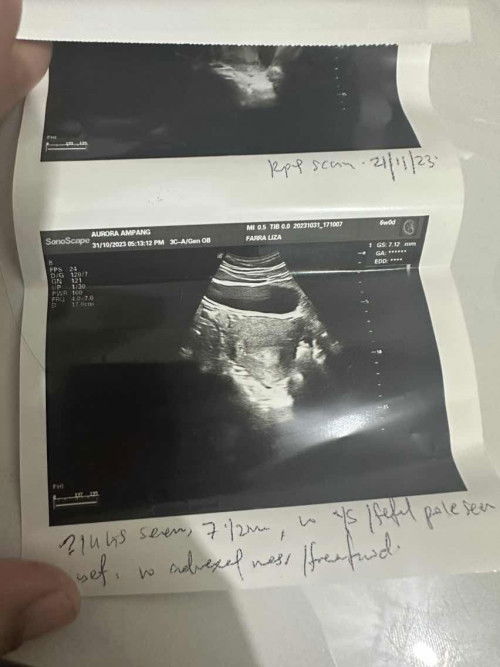

Ikutkan LMP, saya dah 6 weeks 1 days harini. Daripada dapat tahu pregnant masa 4 weeks haritu, Alhamdulillah semua okay. Tapi semalam tetiba ada keluar lendir bercampur dgn darah warna pinkish tapi sikit sangat, itupun sebab saya calit guna tisu sebab lepas kencing. Sebelum ni saya ada history gugur 2 kali. Doc ada scan semalam, dah nampak kantung tapi kecik sangat. Doc kata mcm bukan 6 weeks or salah tarikh sebab daripada lepas gugur, setiap bulan saya period tapi period tu selalu delayed 1 minggu. Mungkin cycle berbeza setiap bulan tu. Skrg ni doc ada bagi Duphaston untuk saya consume & repeat scan after 3 weeks. Harap semuanya baik baik saja🤲🏻